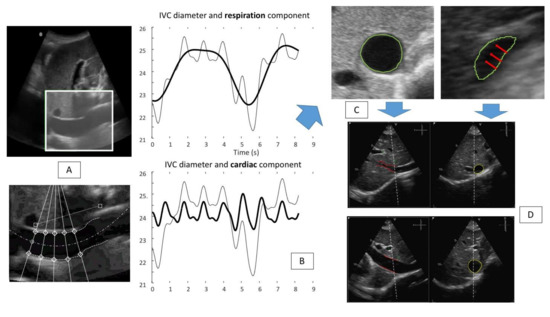

- Mesin, L.; Pasquero, P.; Roatta, S. Multi-directional Assessment of Respiratory and Cardiac Pulsatility of the Inferior Vena Cava From Ultrasound Imaging in Short Axis. Ultrasound Med. Biol. 2020, 46, 3475–3482. [Google Scholar] [CrossRef] [PubMed]

- Mesin, L.; Roatta, S.; Pasquero, P.; Porta, M. Automated Volume Status Assessment Using Inferior Vena Cava Pulsatility. Electronics 2020, 9, 1671. [Google Scholar] [CrossRef]

- Mesin, L.; Giovinazzo, T.; D’Alessandro, S.; Roatta, S.; Raviolo, A.; Chiacchiarini, F.; Porta, M.; Pasquero, P. Improved Repeatability of the Estimation of Pulsatility of Inferior Vena Cava. Ultrasound Med. Biol. 2019, 45, 2830–2843. [Google Scholar] [CrossRef] [PubMed]

- Mesin, L.; Pasquero, P.; Roatta, S. Tracking and Monitoring Pulsatility of a Portion of Inferior Vena Cava from Ultrasound Imaging in Long Axis. Ultrasound Med. Biol. 2019, 45, 1338–1343. [Google Scholar] [CrossRef]

- Ermini, L.; Seddone, S.; Policastro, P.; Mesin, L.; Pasquero, P.; Roatta, S. The cardiac caval index. Improving non-invasive assessment of cardiac preload. J Ultras Med. 2021; in press. [Google Scholar] [CrossRef]

- Mesin, L.; Albani, S.; Sinagra, G. Non-invasive Estimation of Right Atrial Pressure Using Inferior Vena Cava Echography. Ultrasound Med. Biol. 2019, 45, 1331–1337. [Google Scholar] [CrossRef]

- Albani, S.; Pinamonti, B.; Giovinazzo, T.; de Scordilli, M.; Fabris, E.; Stolfo, D.; Perkan, A.; Gregorio, C.; Barbati, G.; Geri, P.; et al. Accuracy of right atrial pressure estimation using a multi-parameter approach derived from inferior vena cava semi-automated edge-tracking echocardiography: A pilot study in patients with cardiovascular disorders. Int. J. Cardiovasc. Imaging 2020, 36, 1213–1225. [Google Scholar] [CrossRef]

- Mesin, L.; Pasquero, P.; Albani, S.; Porta, M.; Roatta, S. Semi-automated tracking and continuous monitoring of inferior vena cava diameter in simulated and experimental ultrasound imaging. Ultrasound Med. Biol. 2015, 41, 845–857. [Google Scholar] [CrossRef][Green Version]